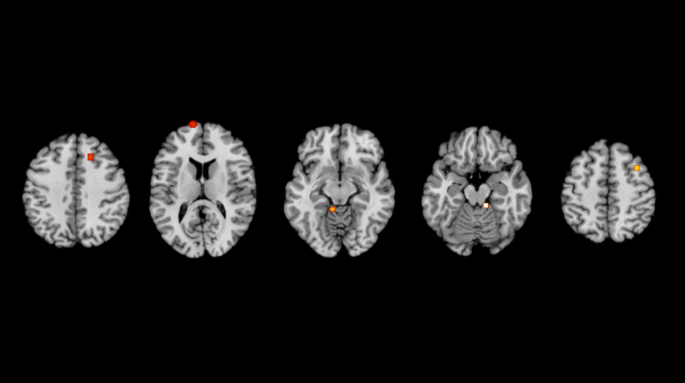

Further subgroup analysis was subsequently performed. The results are shown in Tables 7 and 8; Figs. 5 and 6.

Subgroup analysis according to age

In the activated brain region, 2 studies30,33 (with a total of 10 foci included) were included in the adult group, and the results revealed significant convergence of working memory tasks in the left superior frontal gyrus. The remaining 2 studies involved children and older adult, and thus, they were not analyzed separately.

Subgroup analysis according to exercise type

In the activated brain region, 3 studies30,33,35 (with a total of 15 foci included) were included in the aerobic exercise group, and the results revealed significant convergence of working memory tasks in the left superior frontal gyrus.

Subgroup analysis according to exercise duration

In the activated brain region, 2 studies30,35 (with a total of 8 foci included) were included in the acute exercise group, and the results revealed significant convergence of working memory tasks in the cerebellar hillslope, lingual gyrus, and medial frontal gyrus. 2 studies33,34 (with a total of 9 foci included) were included in the chronic exercise group, and the results revealed significant convergence of working memory tasks in the left superior temporal gyrus, left superior frontal gyrus (BA8), left postcentral gyrus, and left superior frontal gyrus (BA10)(Some coordinates from the same article with aerobic subgroup).

Activation clusters for working memory ALE analysis in standard MNI space. (a) Adult. (b) Acute exercise. (c) Chronic exercise. (d) Aerobic exercise.

Activation clusters for working memory ALE analysis in standard MNI space.